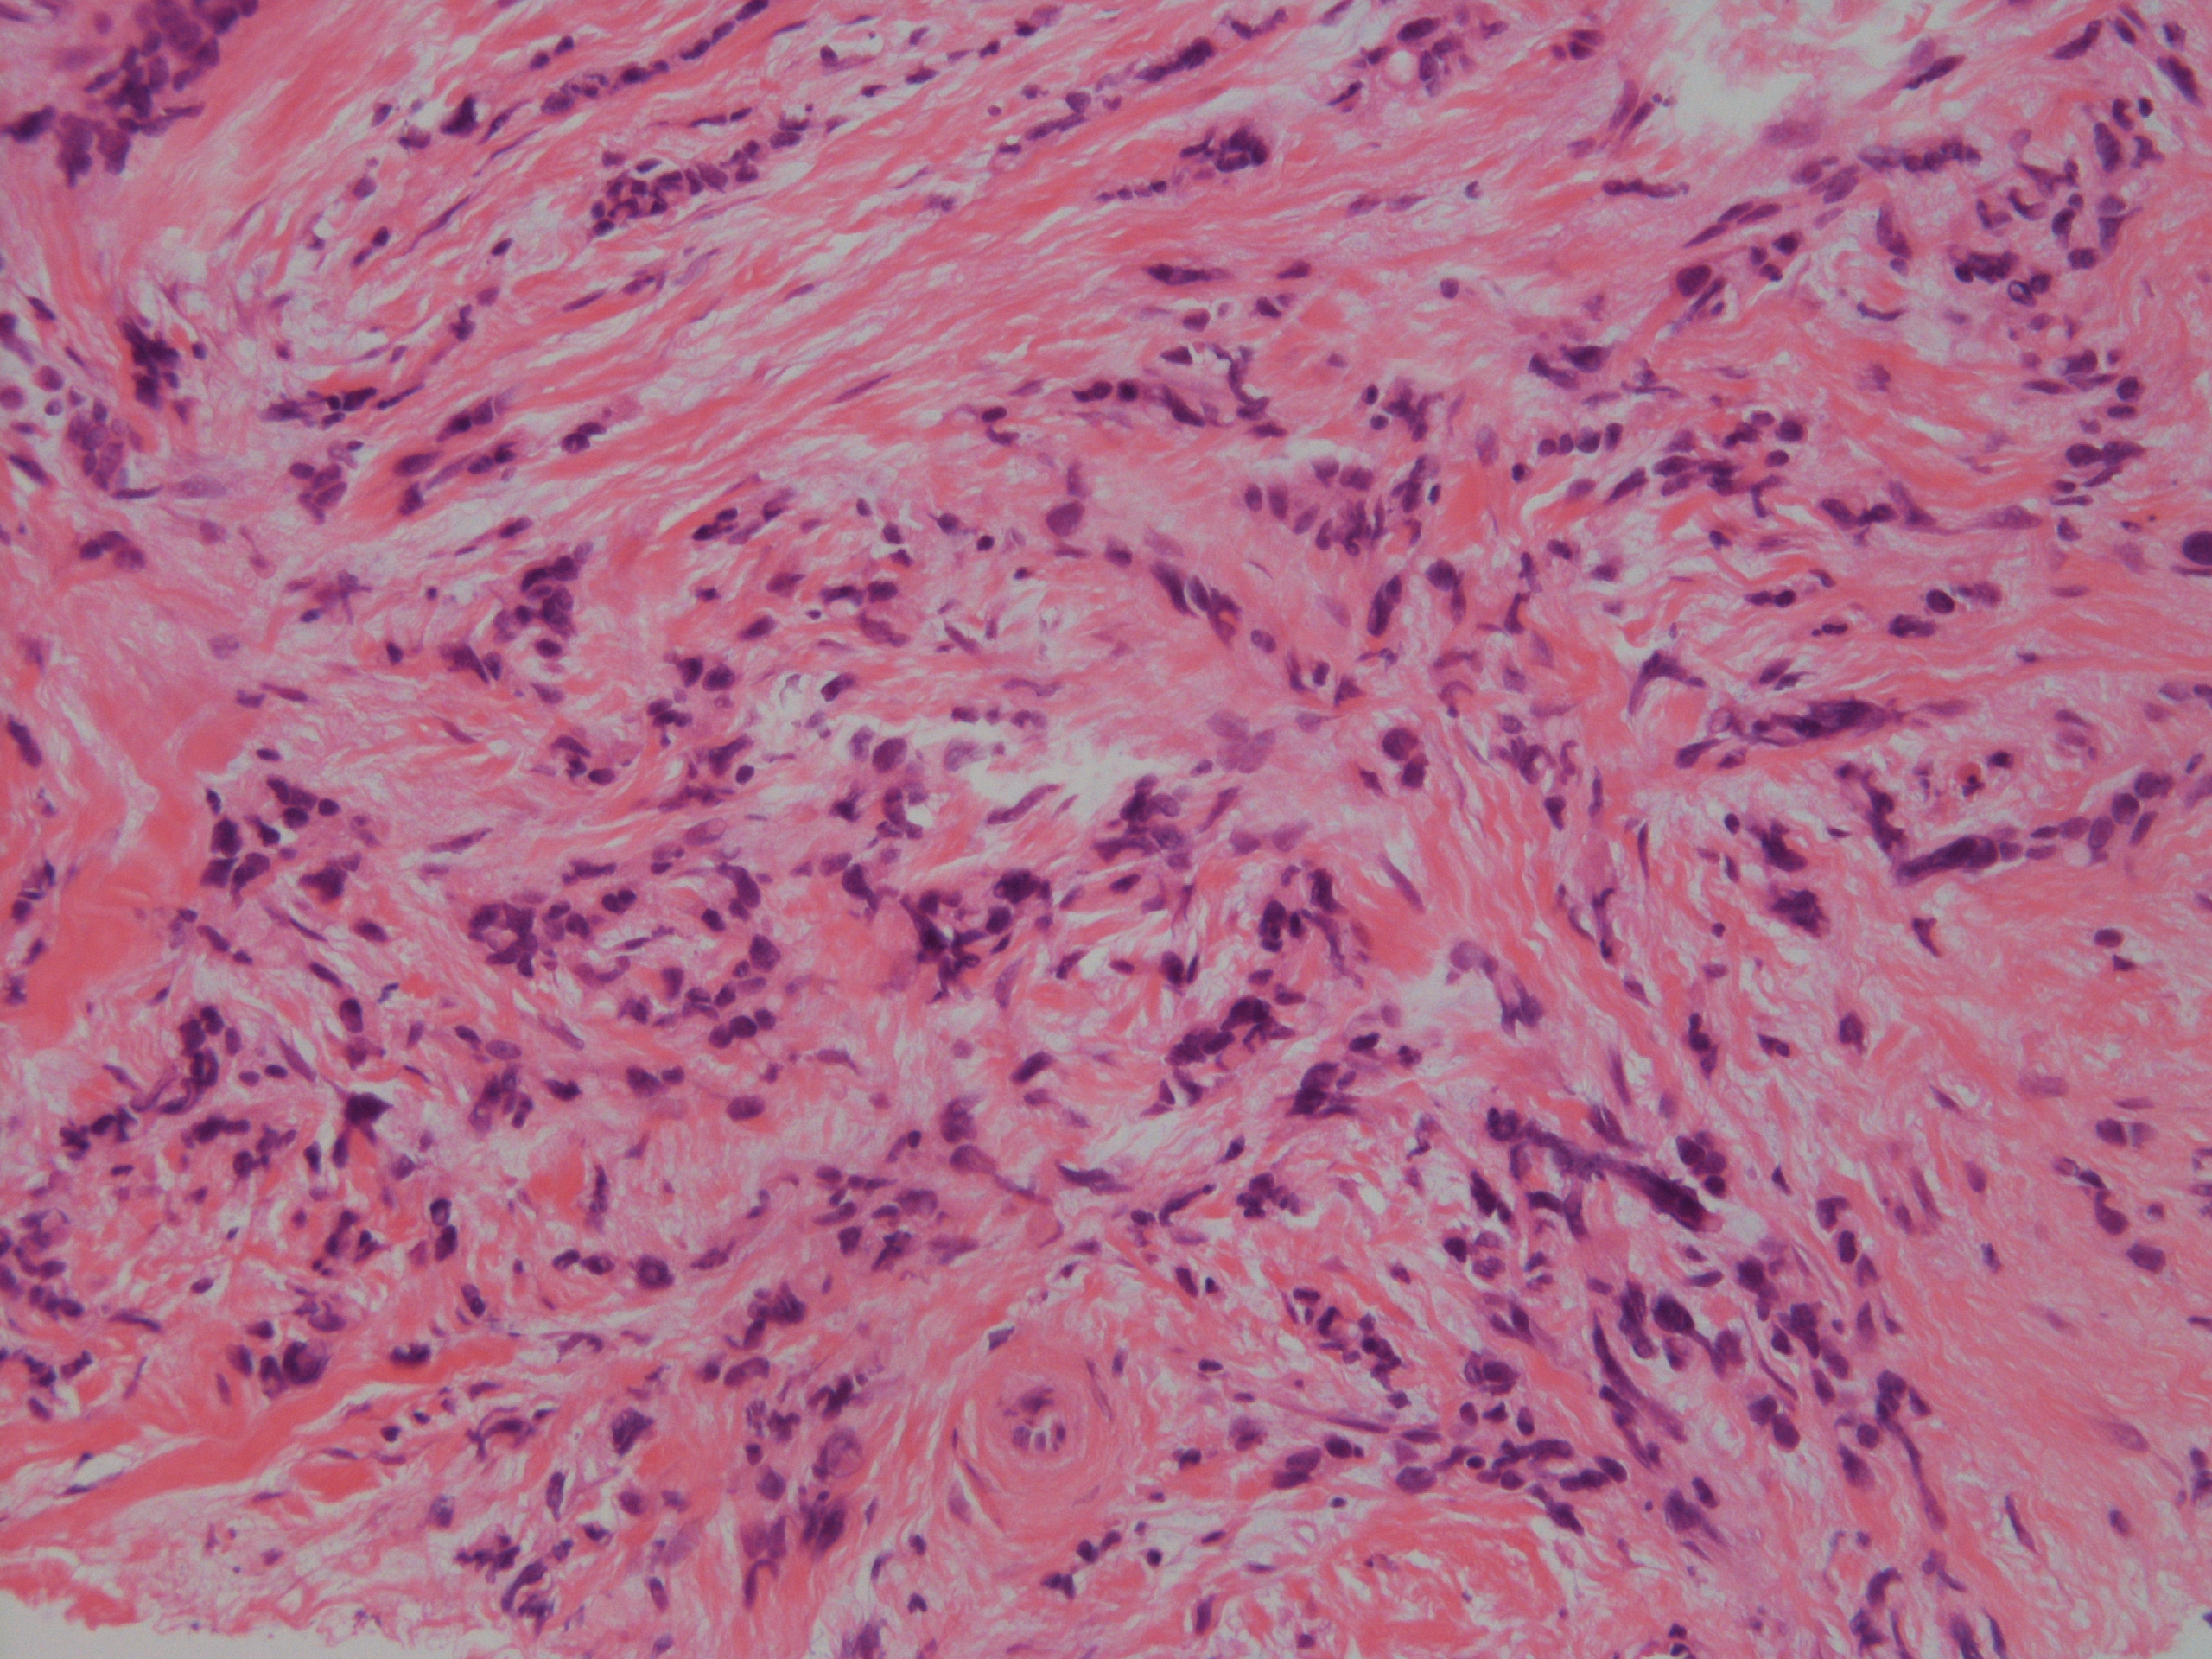

[組織所見]

組織では免疫染色も含め総合的に浸潤部は小葉癌(ER+、 HER2-)であったが、

乳管内癌成分においてもE-cadherinの染色性が減弱しており、非浸潤性乳管癌か非浸潤性小葉癌(多形型)か判断が難しいが、

乳管内癌成分はER-、HER2(3+)で形質発現はクリアカットに分かれ、最終的に非浸潤性乳管癌と診断された。